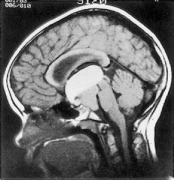

脑积水 ,是一种大脑和脊髓周围有额外的脑脊液的情况。脑脊液...

在产前发育过程中,大脑从管状结构开始。随着它的生长,内管...

医学治疗脑积水是用来推迟手术干预。它可能用于早产儿出血性...